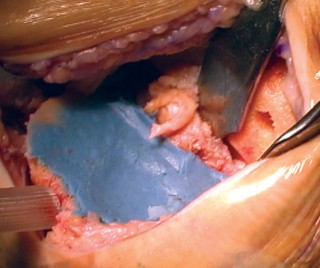

الخطوة 1: التحضير الأولي والوصول إلى المفصل

الوصول إلى المفصل (الشقوق):

يستخدم الأستاذ الدكتور محمد هطيف عادةً نهجًا جراحيًا طفيف التوغل (abbreviated trivector approach) للوصول إلى الركبة.

- يتم عمل شق جراحي يبدأ من الجزء الإنسي للحدبة الظنبوبية ويمتد إلى الجزء العلوي من الرضفة.

- يتم فصل ارتباط العضلة المتسعة الإنسية عن وتر العضلة الرباعية، مع الحرص على عدم تجاوز 3 سم فوق القطب العلوي للرضفة.

- يتم رفع غشاء الأنسجة الرخوة الإنسي بعناية وصولاً إلى الزاوية الخلفية الإنسية للركبة.

- يتم إزالة جزء من الوسادة الدهنية للرضفة.

- تُدفع الرضفة بعد ذلك إلى الميزاب الجانبي وتُثنى الركبة لزيادة كشف المفصل.